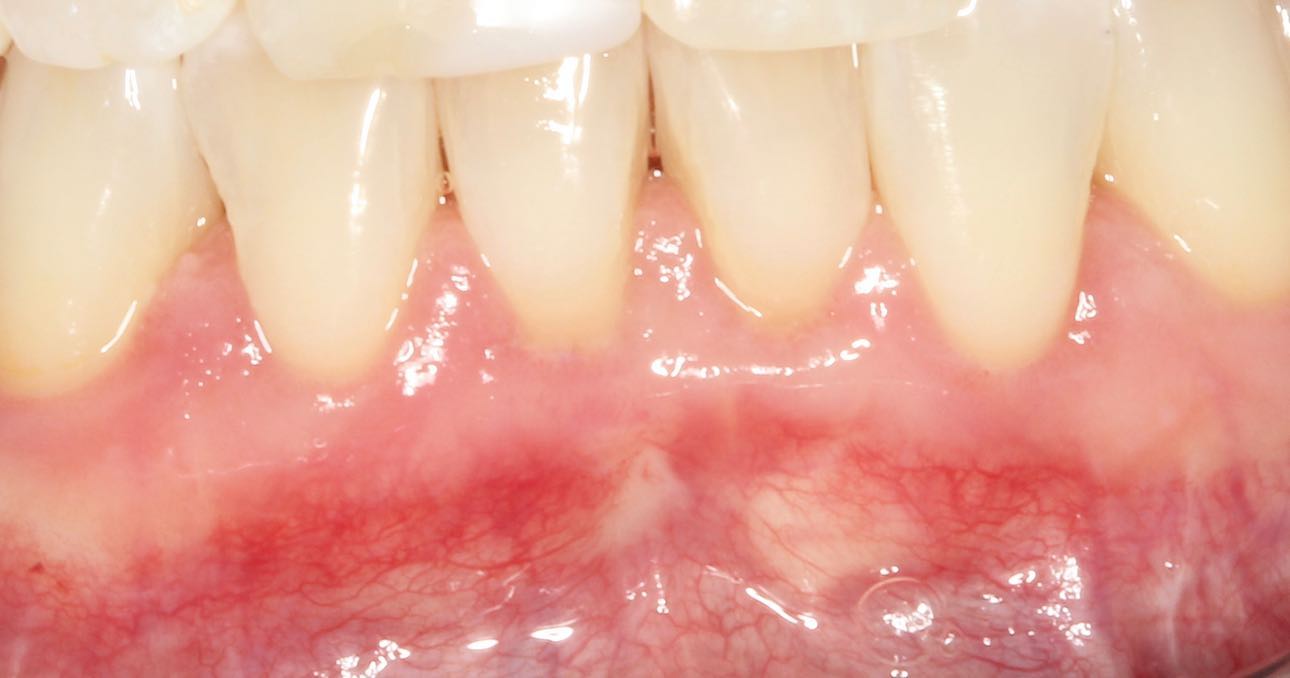

Allograft Dermal with Pinhole Surgery, Alternative to Gum Grafting

Connective Tissue Gingival Grafting for Gingival Recession